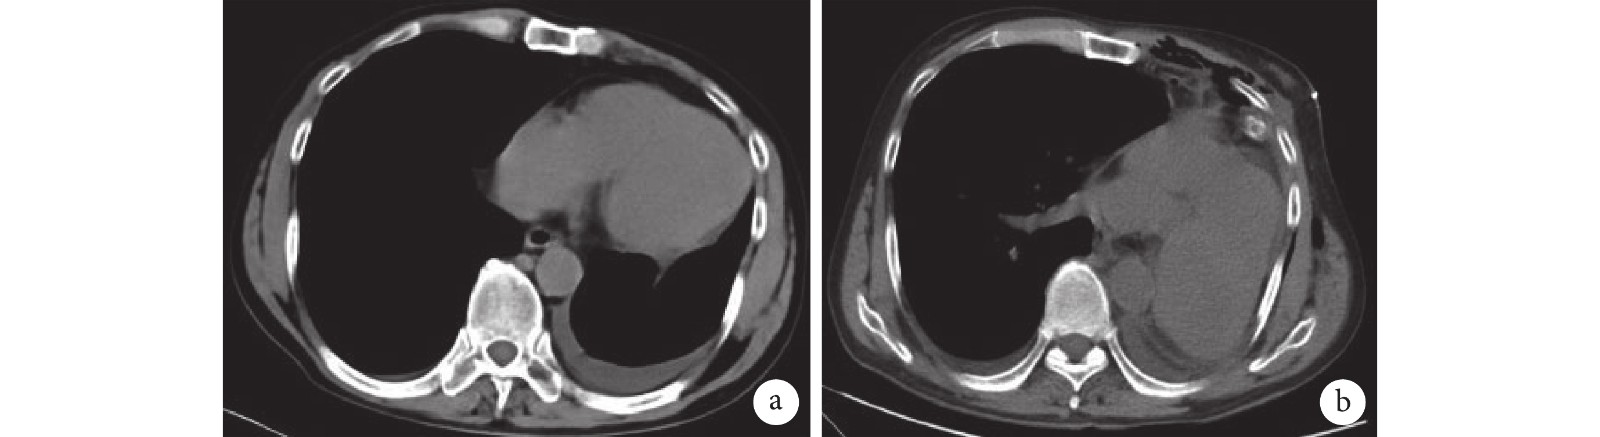

a:術前 CT 顯示心臟異常向左延伸,但左側心包缺損并不明顯;b:術后復查 CT 顯示心臟繞腔靜脈順時針轉位

雖然本例患者術中頻繁出現心律失常和低血壓,但都能在向心臟表面噴灑利多卡因并暫停手術幾分鐘后恢復正常。盡管患者術后復查 CT 提示心臟向左側胸腔扭轉(圖 3),但術后 6 個月內無低血壓或心律失常等癥狀。手術過程順利,術中無組織臟器損傷,整體效果滿意,我們認為,對于無癥狀的完全左側心包缺損患者,全肺切除術是可行的。